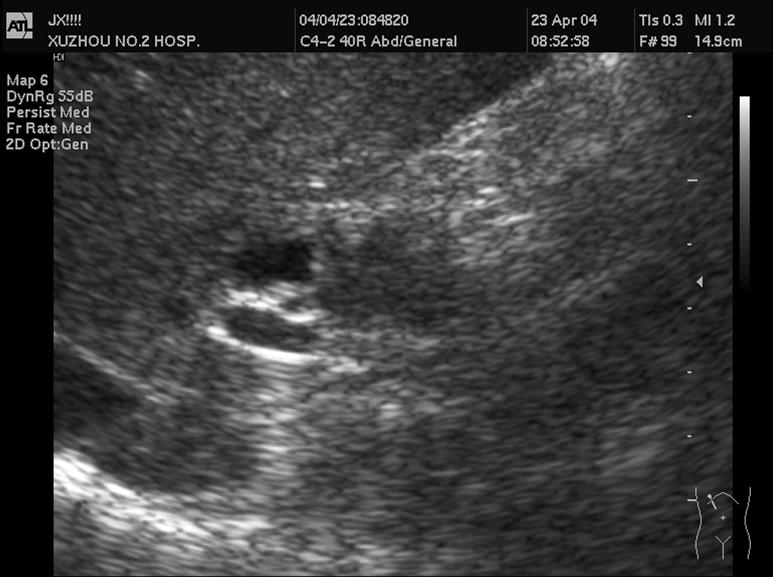

4 胆道蛔虫病